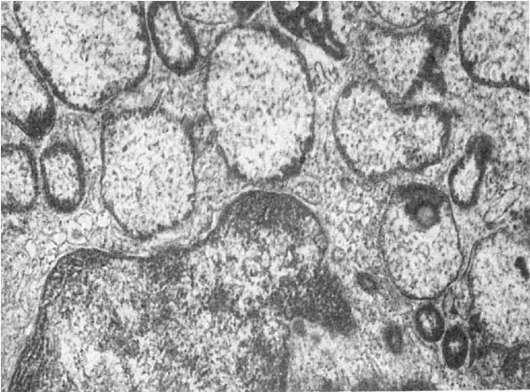

Рис.

18. Фаголизосомы в гепатоцитах. х18 500